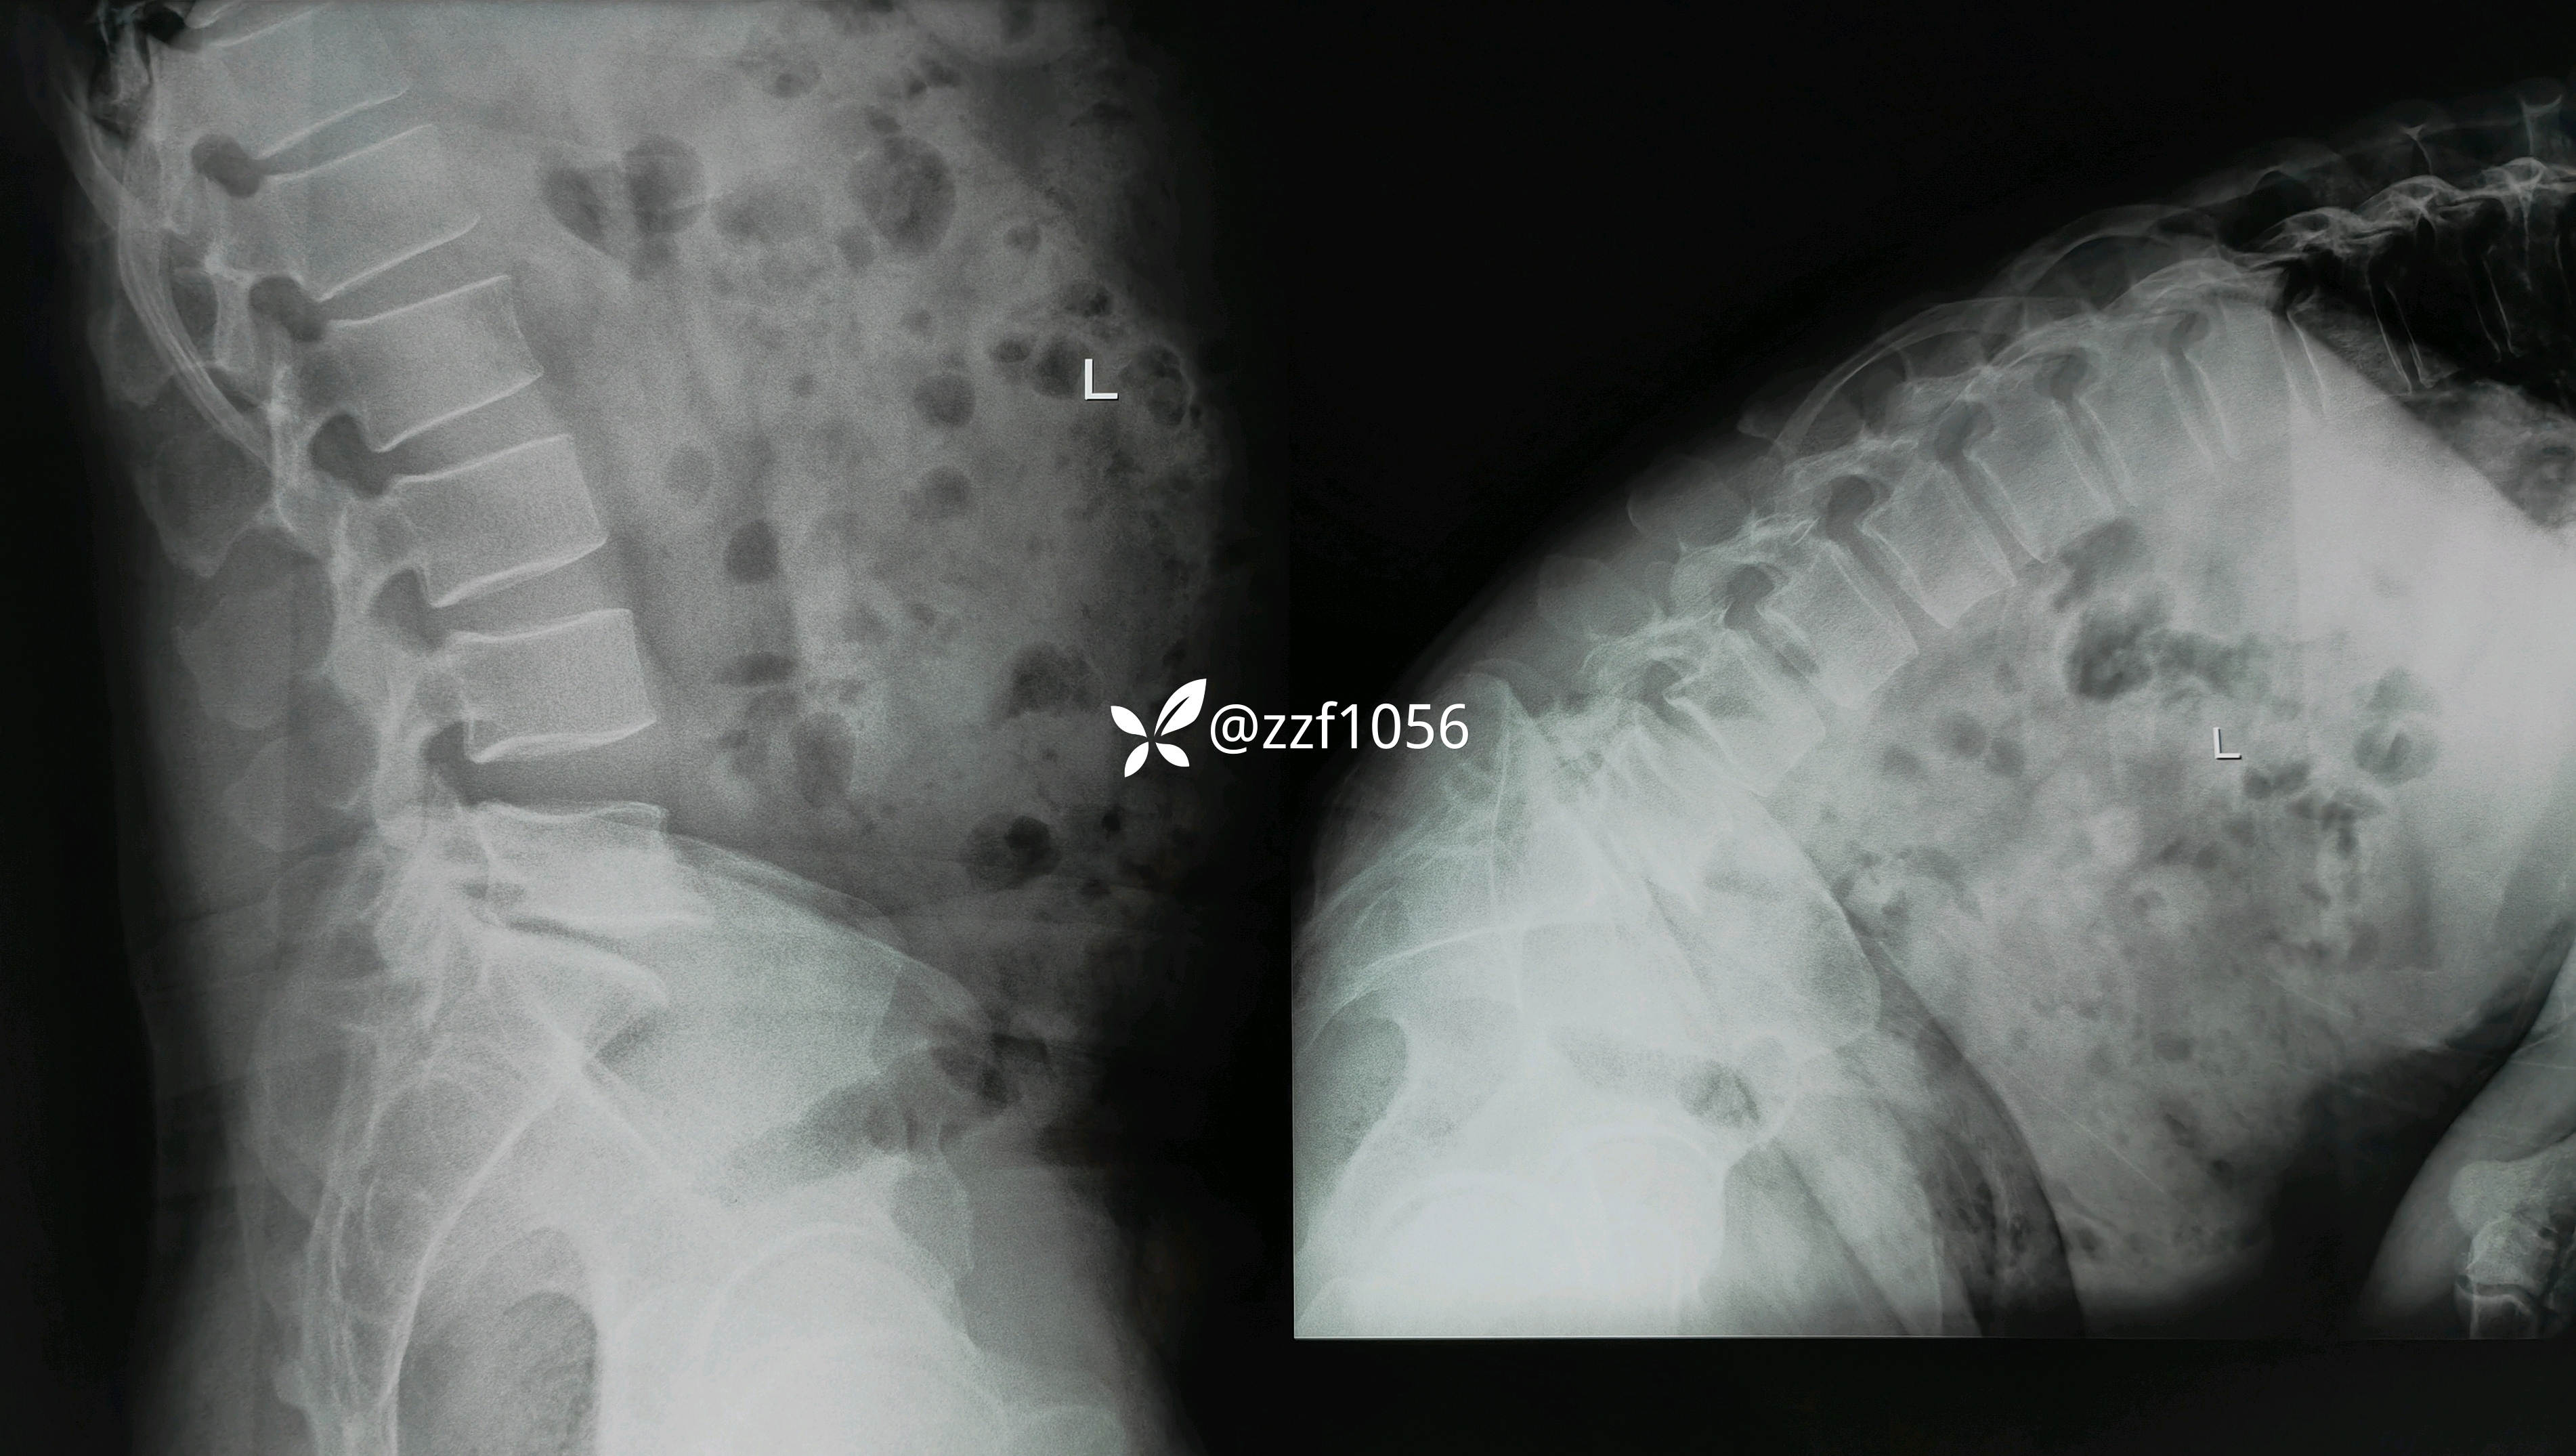

极外侧突出吗

影像上可看到L5/S1间隙非常狭窄,退变严重,两侧均有神经根激惹,椎间孔狭窄,L5下终板终板炎较重,左下肢无任何症状,右下肢L5S1根症状均存在,建议椎间孔镜下减压L5根和S1根,患者拒绝,因咨询多家医院要求开放融合。